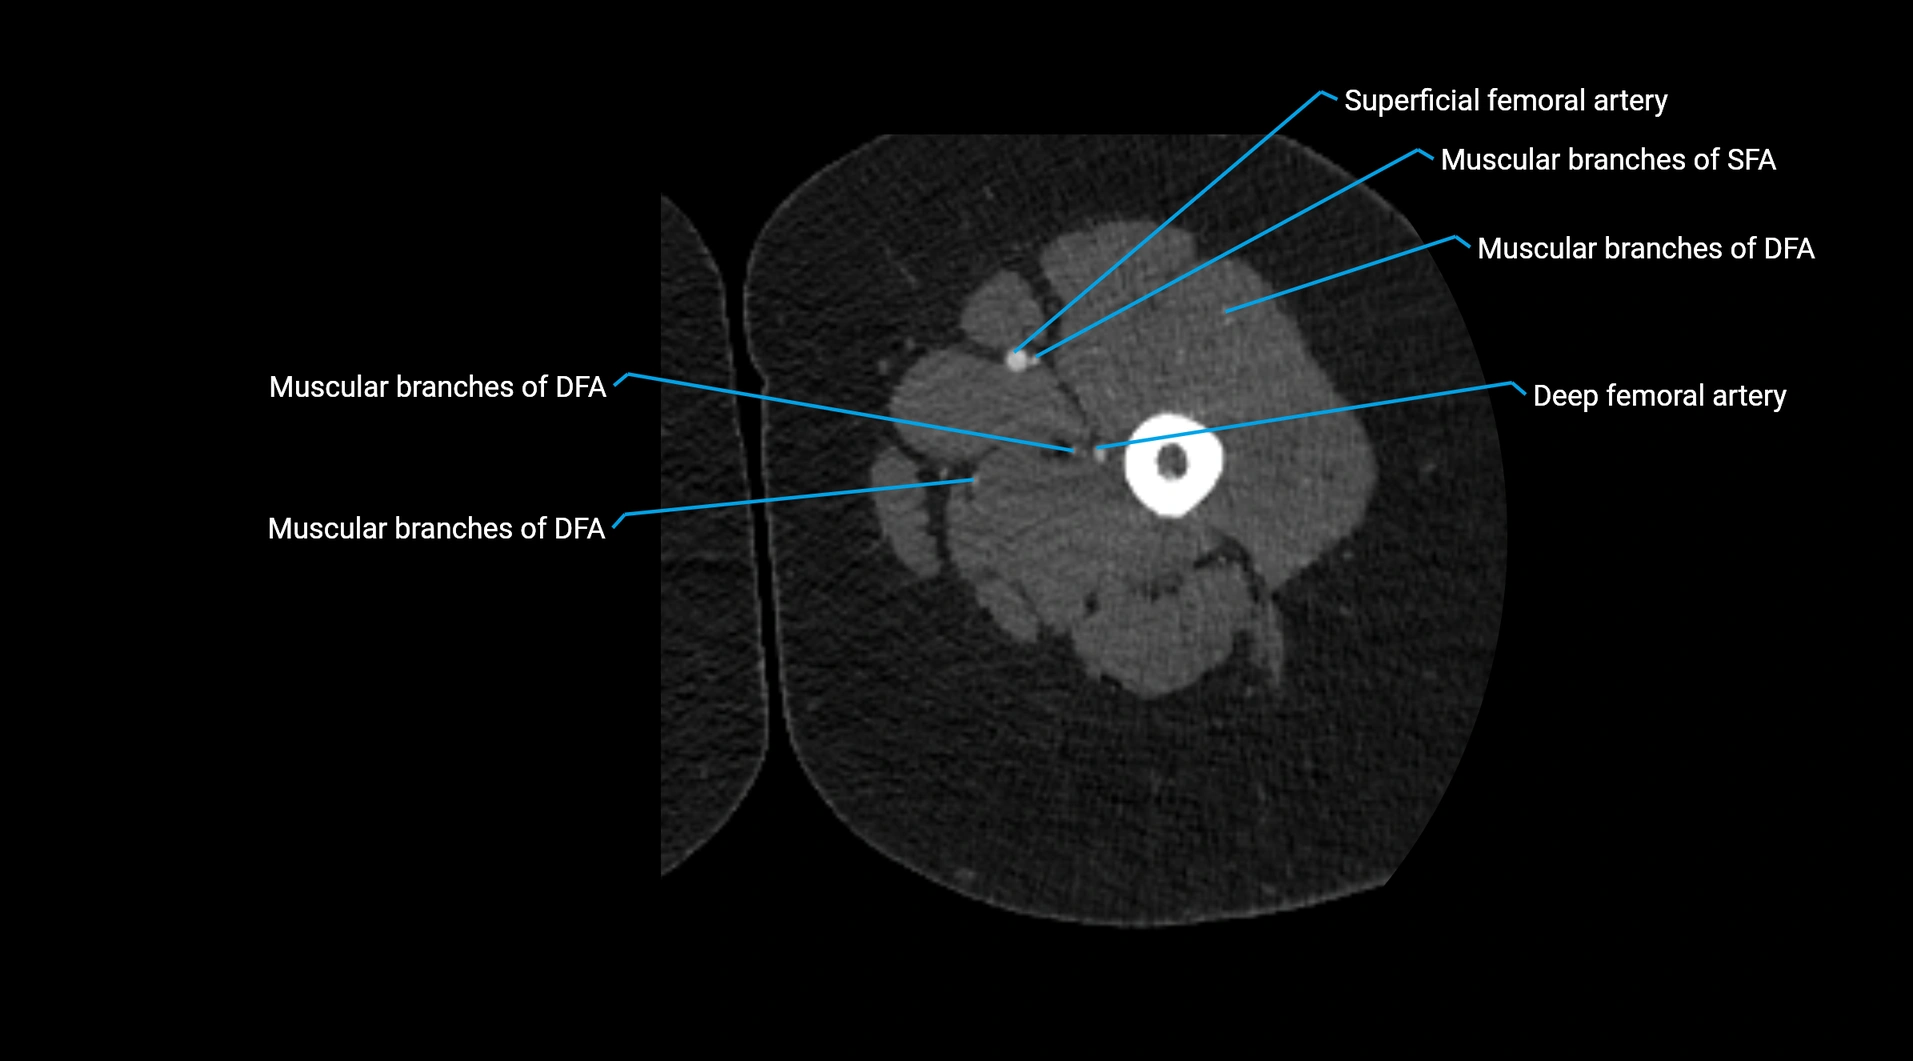

CT images

image